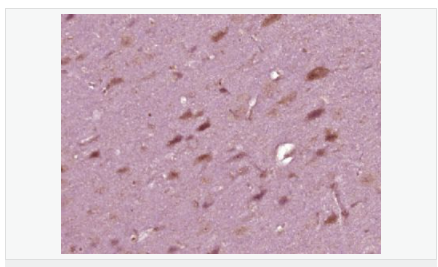

交叉反應(yīng):Rat,Mouse,Human(predicted:Sheep,Rabbit,Horse,Cow,Pig) 推薦應(yīng)用:IHC-P,ELISA

| 產(chǎn)品應(yīng)用 | ELISA=1:5000-10000 IHC-P=1:100-500 (石蠟切片需做抗原修復(fù)) not yet tested in other applications. optimal dilutions/concentrations should be determined by the end user. |